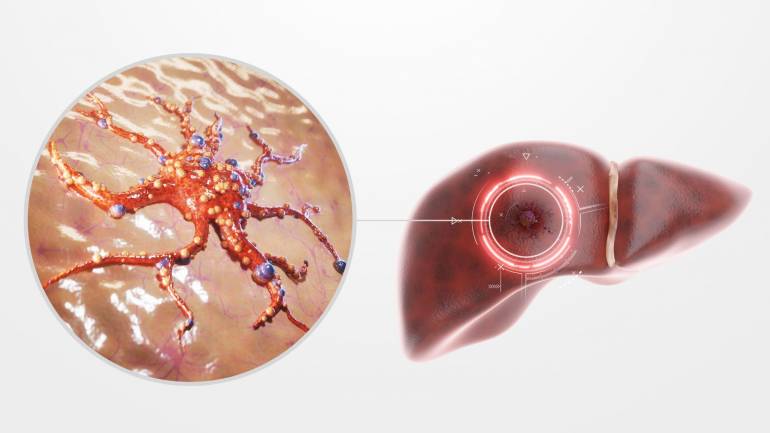

ภาพประกอบข่าว

ภาพประกอบข่าว

ระยะ 4 ตับแข็ง (Cirrhosis) หรือมะเร็งตับ ตับเสียหายถาวร มีพังผืดหนาแน่นหรือตับแข็ง อาจนำไปสู่มะเร็งตับ ต้องรักษาด้วยยา การผ่าตัด หรือเปลี่ยนตับ และมีความเสี่ยงเสียชีวิตสูง